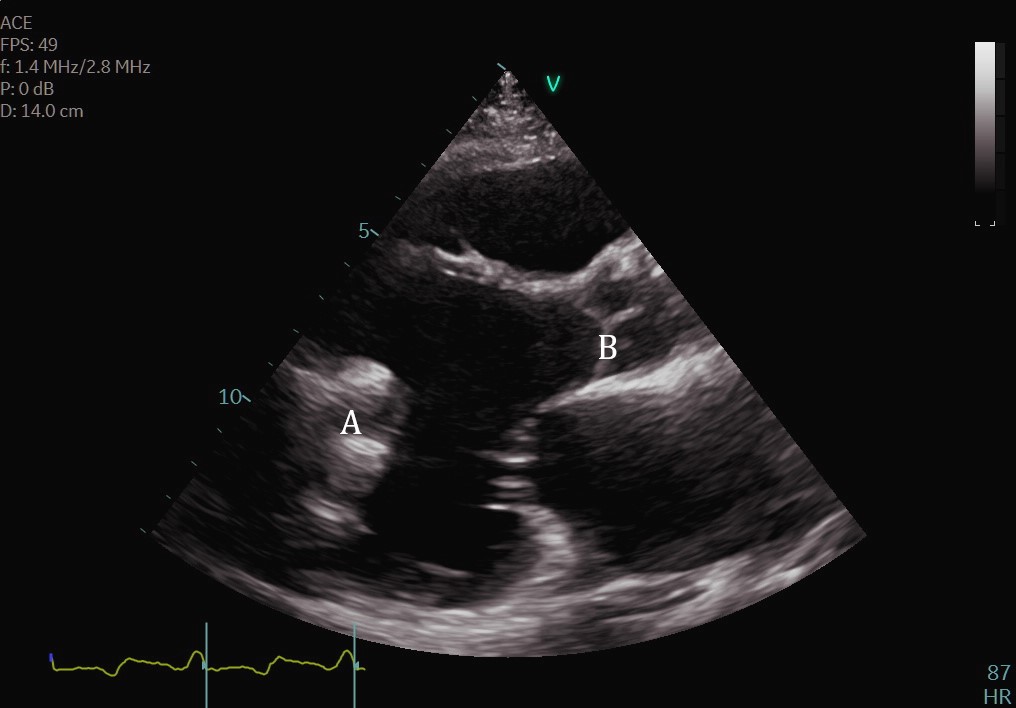

Additionally, an assessment for intracardiac thrombi is of critical importance in the preoperative setting (Fig. 17). While the presence of intracardiac thrombus is not an absolute contraindication, it may increase the risk of embolic events during cannulation [47]. Patients with severely decreased ejection fraction or with a left ventricular aneurysm are at increased risk of developing thrombi. The use of ultrasound enhancing agents can be useful for improved detection of intracardiac thrombi [26]. Transesophageal echocardiography (TEE) may be needed for further delineation of the left atrial appendage in patients with atrial fibrillation.

Fig. 17.Apical 4-chamber TTE images demonstrated a large LV thrombus (A) attached to the lateral wall. (B) LV.